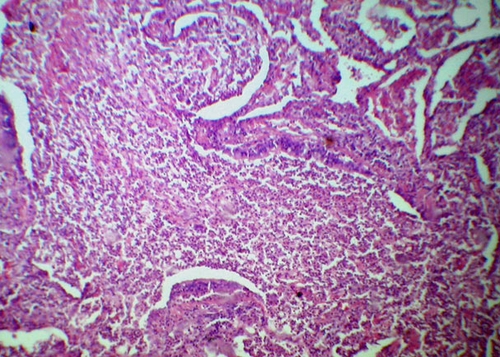

Рентгенодиагностика бронхопневмонии: Советы и примеры

Раздел: Альбом открытий